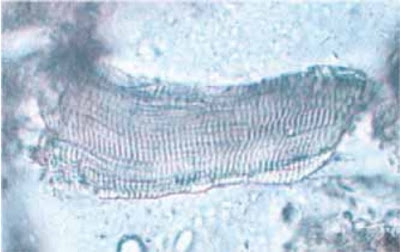

هو muscle fibers يظهرمن تناول اللحوم ،مميز وواضح. (مثل شكل الحصيرة ) ولا يختلط مع اي شيء آخر في البراز ويمكن تقديره بسهولة